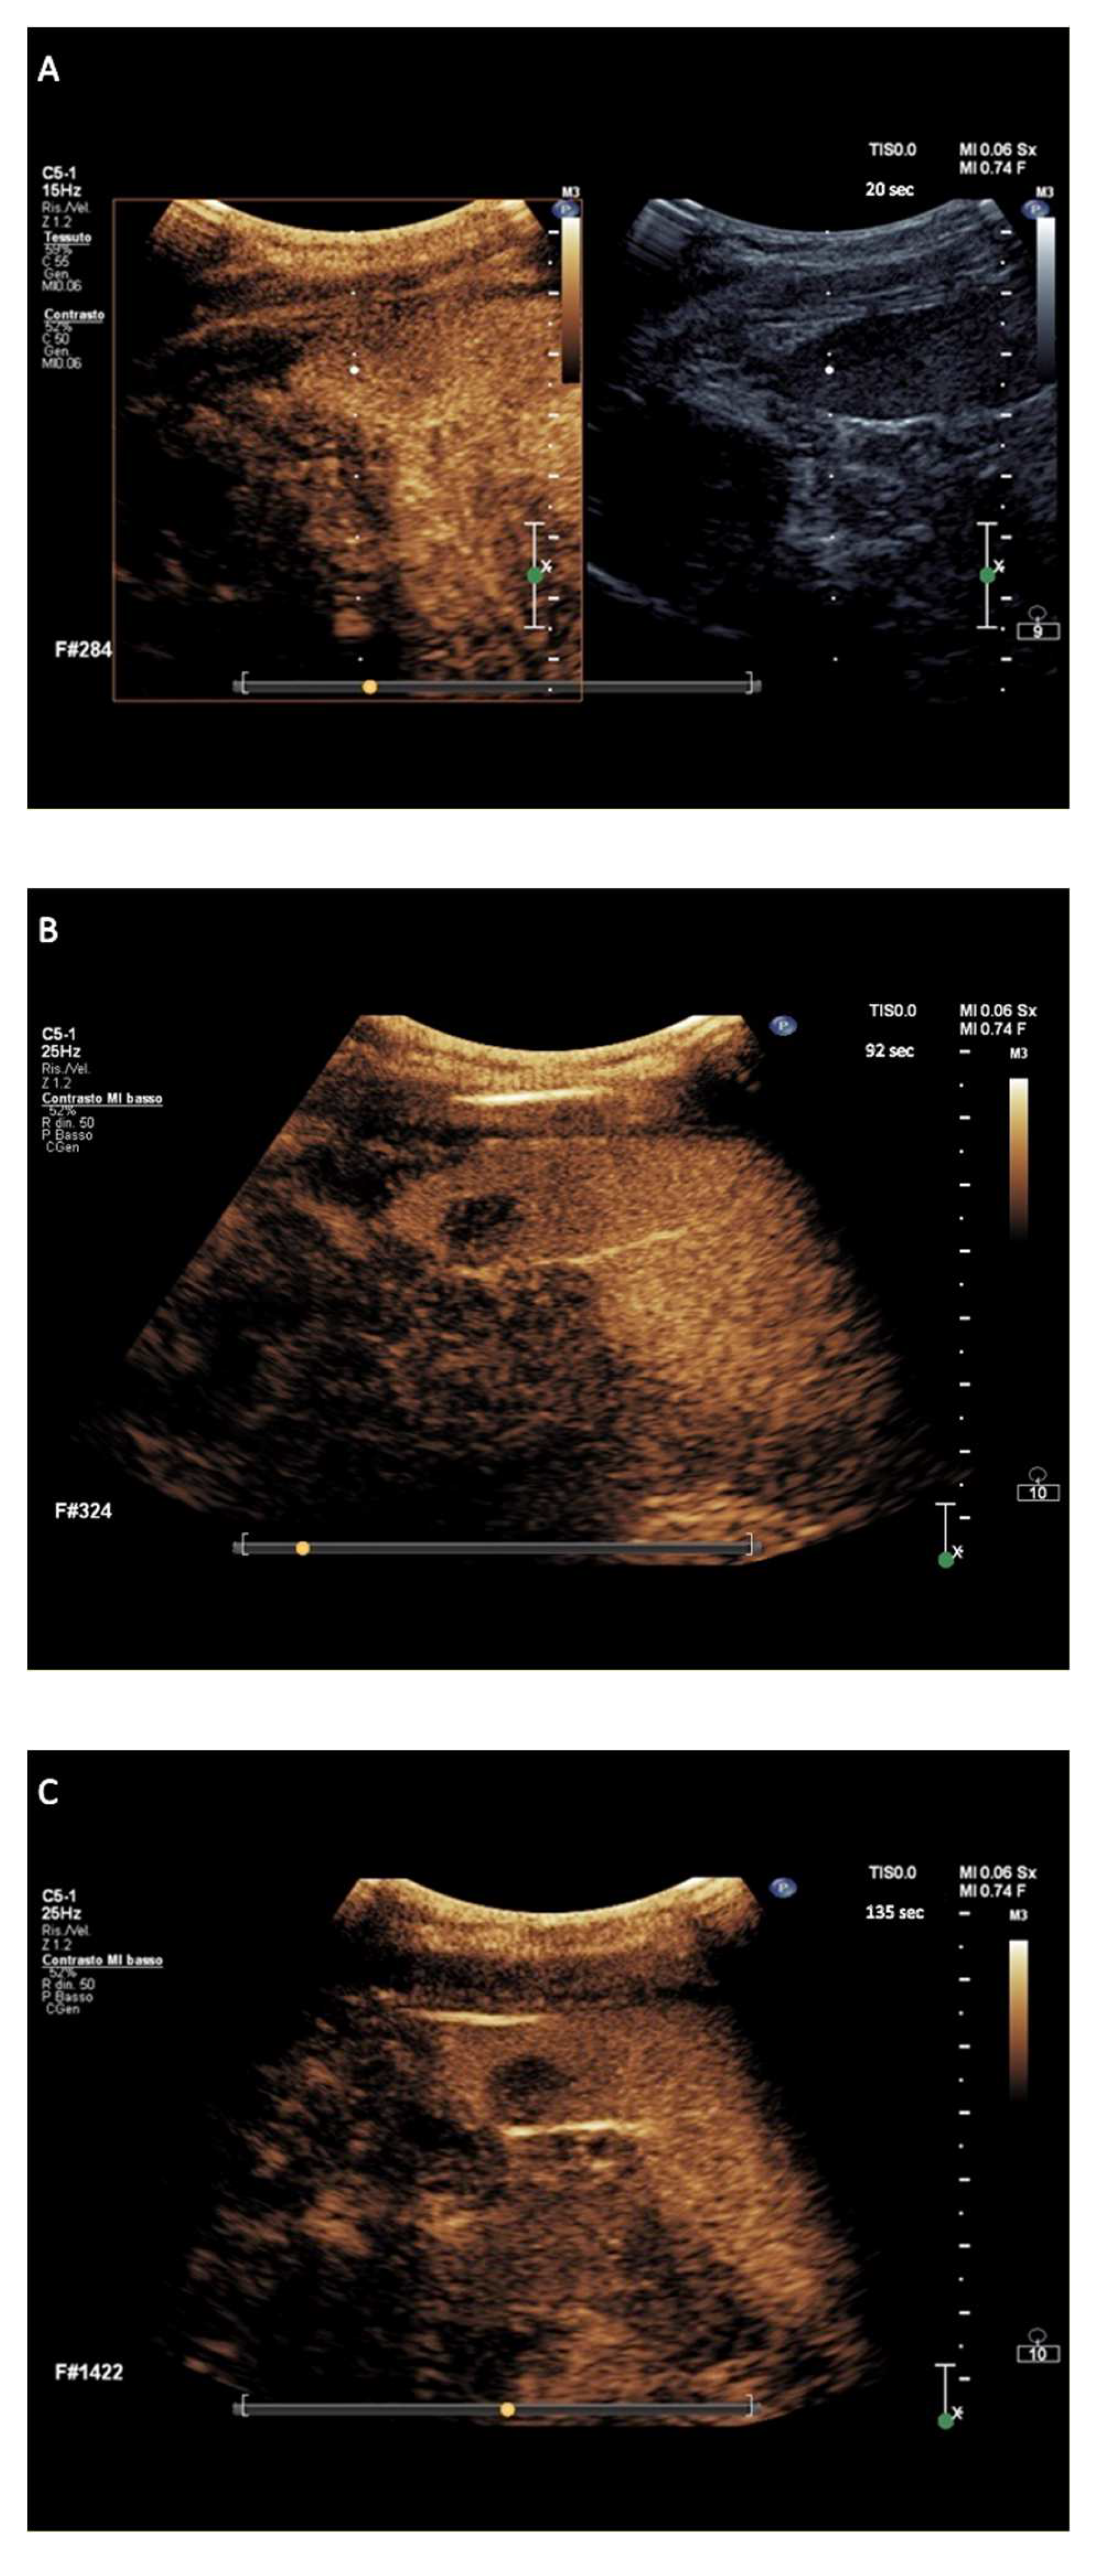

a-NHL nodules displayed isoenhancement in the arterial phase followed by wash-out appearance that had early onset and marked degree within <90 s following contrast agent injection, in a total of 122/122 (100%) nodules (Figure 2). The wash-out onset of the 122 nodules of exploratory a-NHL-DC occurred at a median of 42 s (range 20–55 s) with a median of marked wash-out of 74 s (range 55–90 s).

Figure 2.

Major features of CEUS according to the exploratory diagnostic criteria. (A–C) showing aggressive non-Hodgkin lymphoma nodule with very marked wash-out, at 87 s from contrast agent injection.

The hallmark sign of lymphomatous nodular infiltration of spleen consisted of arterial phase isoehnacement followed by early (<60 s) and marked (≤120 s) wash-out appearance of sulfur exafluoride microbubbles. This finding validated the effectiveness of temporal CEUS enhancement and wash-out criteria to establish the diagnosis of involvement by lymphoma. The three principal clinical subtypes of lymphomas analyzed in the study, i.e., a-NHL, c-HL, and i-NHL, were differentiated on the basis of the degree of wash-out intensity (from contrast injection) of nodules. The totality of a-NHL nodules was categorized according to the typical wash-out appearance of very marked degree, i.e., within <90 s following contrast agent injection (Figure 2A–C) resulting in a PPV of 100% (95% CI, 97–100%). Most c-HL nodules tended to be categorized in wash-out appearance of discretely marked degree, i.e., between 90 and 110 s following contrast agent injection (Figure 3A–C), with PPV of 96.6% (95% CI, 88.3–99.6%). Most i-NHL nodules tended to segregate in a diagnostic category characterized by a wash-out appearance that was sufficiently marked in degree, i.e., between >110 and ≤120 s following contrast agent injection (Figure 4A–C), with PPV of 77% (95% CI, 46.2–95%).